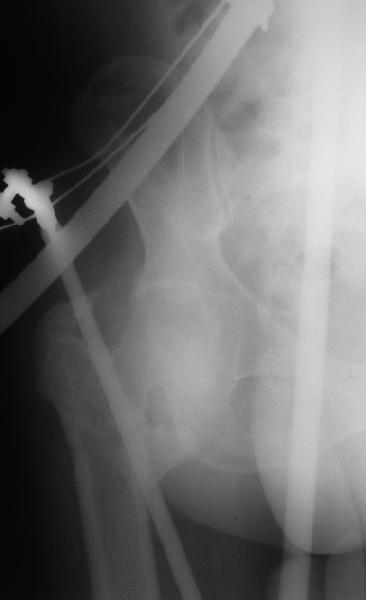

На прошлой неделе оперировали похожего пациента. 2 года после

неудачного остеосинтеза PFN в другом регионе. После удаления остатков

железа выявилось несращение вертельной области.

В такой ситуации важно устранить варусную деформацию. При

использовании гвоздя это непросто. Поэтому в число рассматриваемых

вариантов стоило бы включить вальгизирующую остеотомию с фиксацией

130-градусной клинковой пластиной или DHS.

Поскольку в нашем случае выявилась подвижность, мы наложили дистрактор

таз-бедро на 3 дня, и сделали остеосинтез гаммой без остеотомии. То,

что произошла "корригирующая остеоклазия" в подвертельной области,

выявили после введения гвоздя. Пациент уже уехал домой, будем

наблюдать.